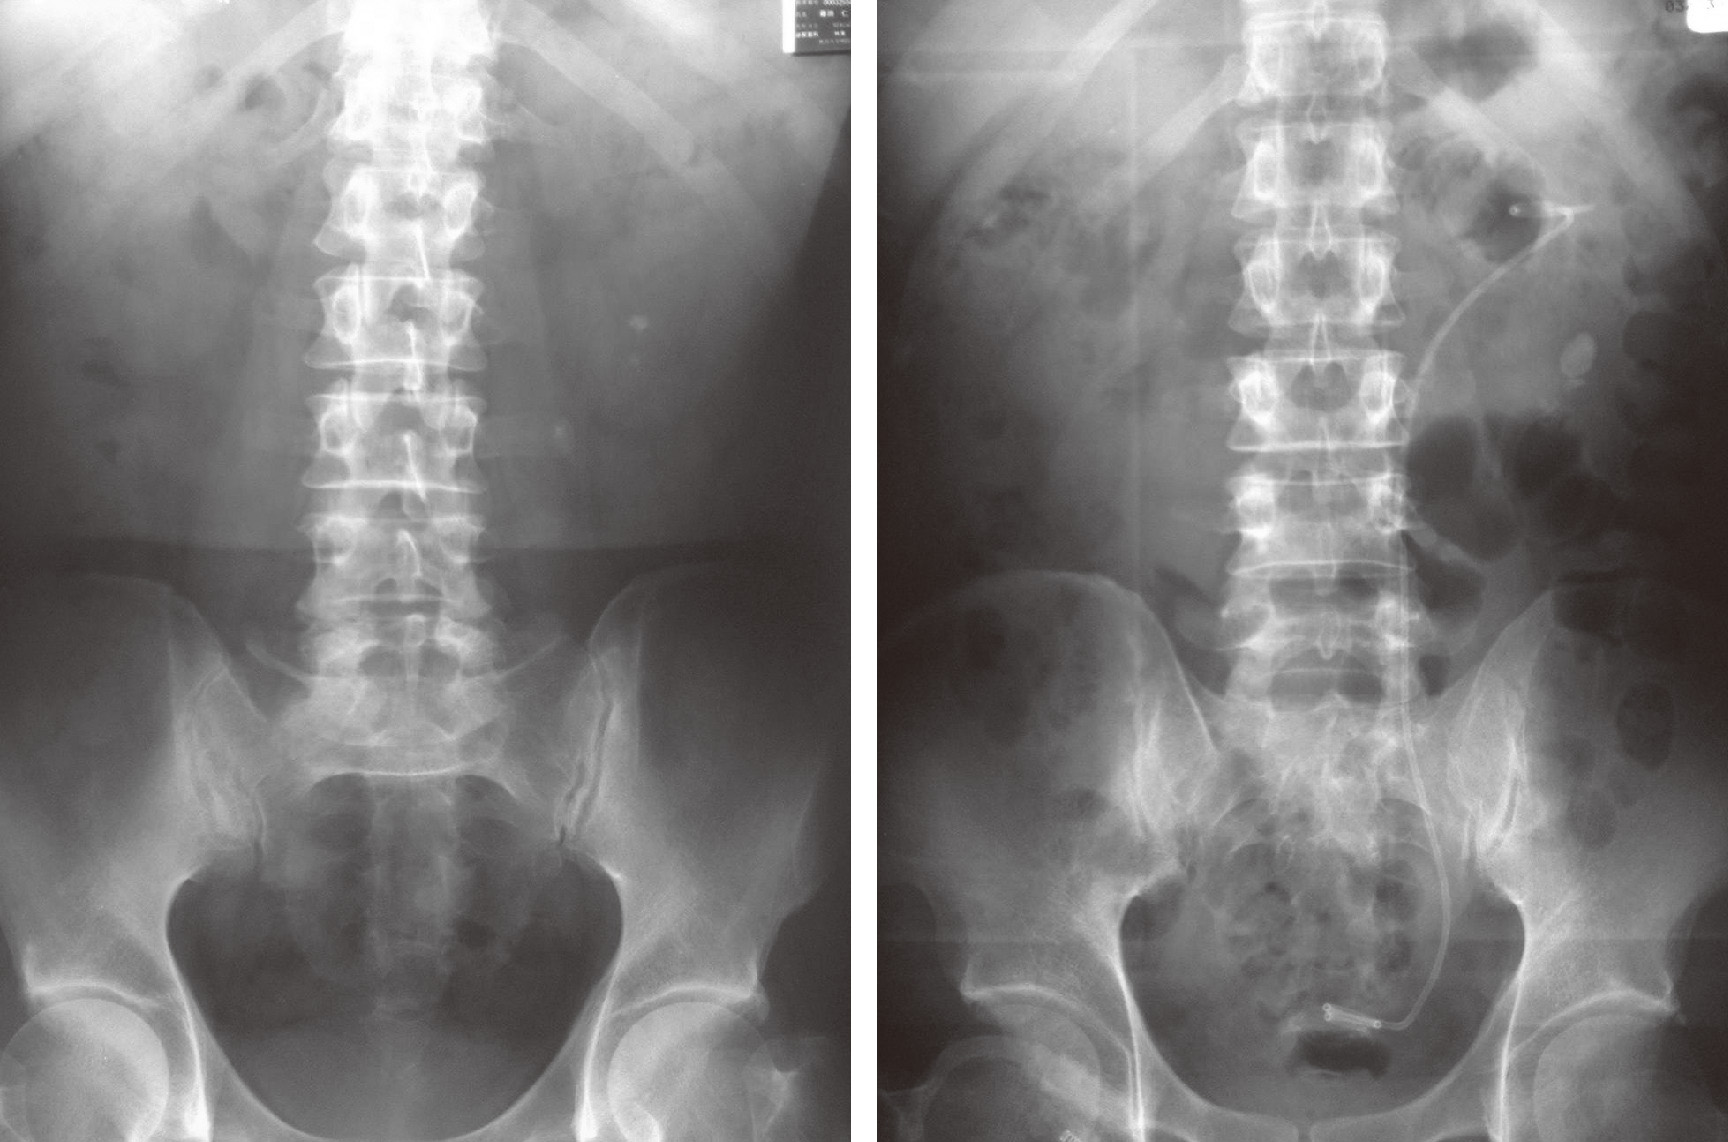

結石破砕治療の実際 – Radiology@Home。尿路結石の治療について | 医療法人社団實理会 東京国際大堀病院。尿路結石外来|尼崎市 おかだ腎泌尿器・ペインクリニック| 阪神。ぷっち おまとめ2袋 白米10キロ。尿路結石症(腎結石・尿管結石)の治療法 - 船橋クリニック 千葉。体外衝撃波結石破砕装置(ESWL)|焼津市立総合病院。尿路結石の検査 - 船橋クリニック 千葉県泌尿器科 尿路結石症。痛みを乗り越えた者だけが手にする秘宝商品説明これは単なる石ではありません。長きにわたり忍耐と痛みを経験した末、身体から生まれた奇跡の結晶です。賢者の石と呼ばれるにふさわしい、神秘的な輝きを放つ逸品!その力強い存在感は、あなたのコレクションに一層の深みを与えることでしょう。おすすめポイント•世界に一つだけのオリジナル品!•痛みを耐え抜いた歴史を感じられるストーリー付き•お守りやアクセサリーの材料にも最適こんな方におすすめ!•面白グッズ好きな方•他人とは違うコレクションを目指す方•人生の痛みを乗り越える象徴が欲しい方これを手にすることで、あなたも「賢者」の仲間入りを果たせるかも?一点限りの出品ですので、お見逃しなく!。尿管結石の最新治療技術 - Genspark。尿路結石症 – 社会医療法人 北腎会 坂泌尿器科千歳クリニック。尿管結石の最新治療技術 - Genspark。巨大腎結石への挑戦 | 研究報告 | 医療法人社団實理会 東京国際。尿路結石(尿管結石、腎臓結石、膀胱結石)の原因や治療について。尿路結石」について|市立貝塚病院